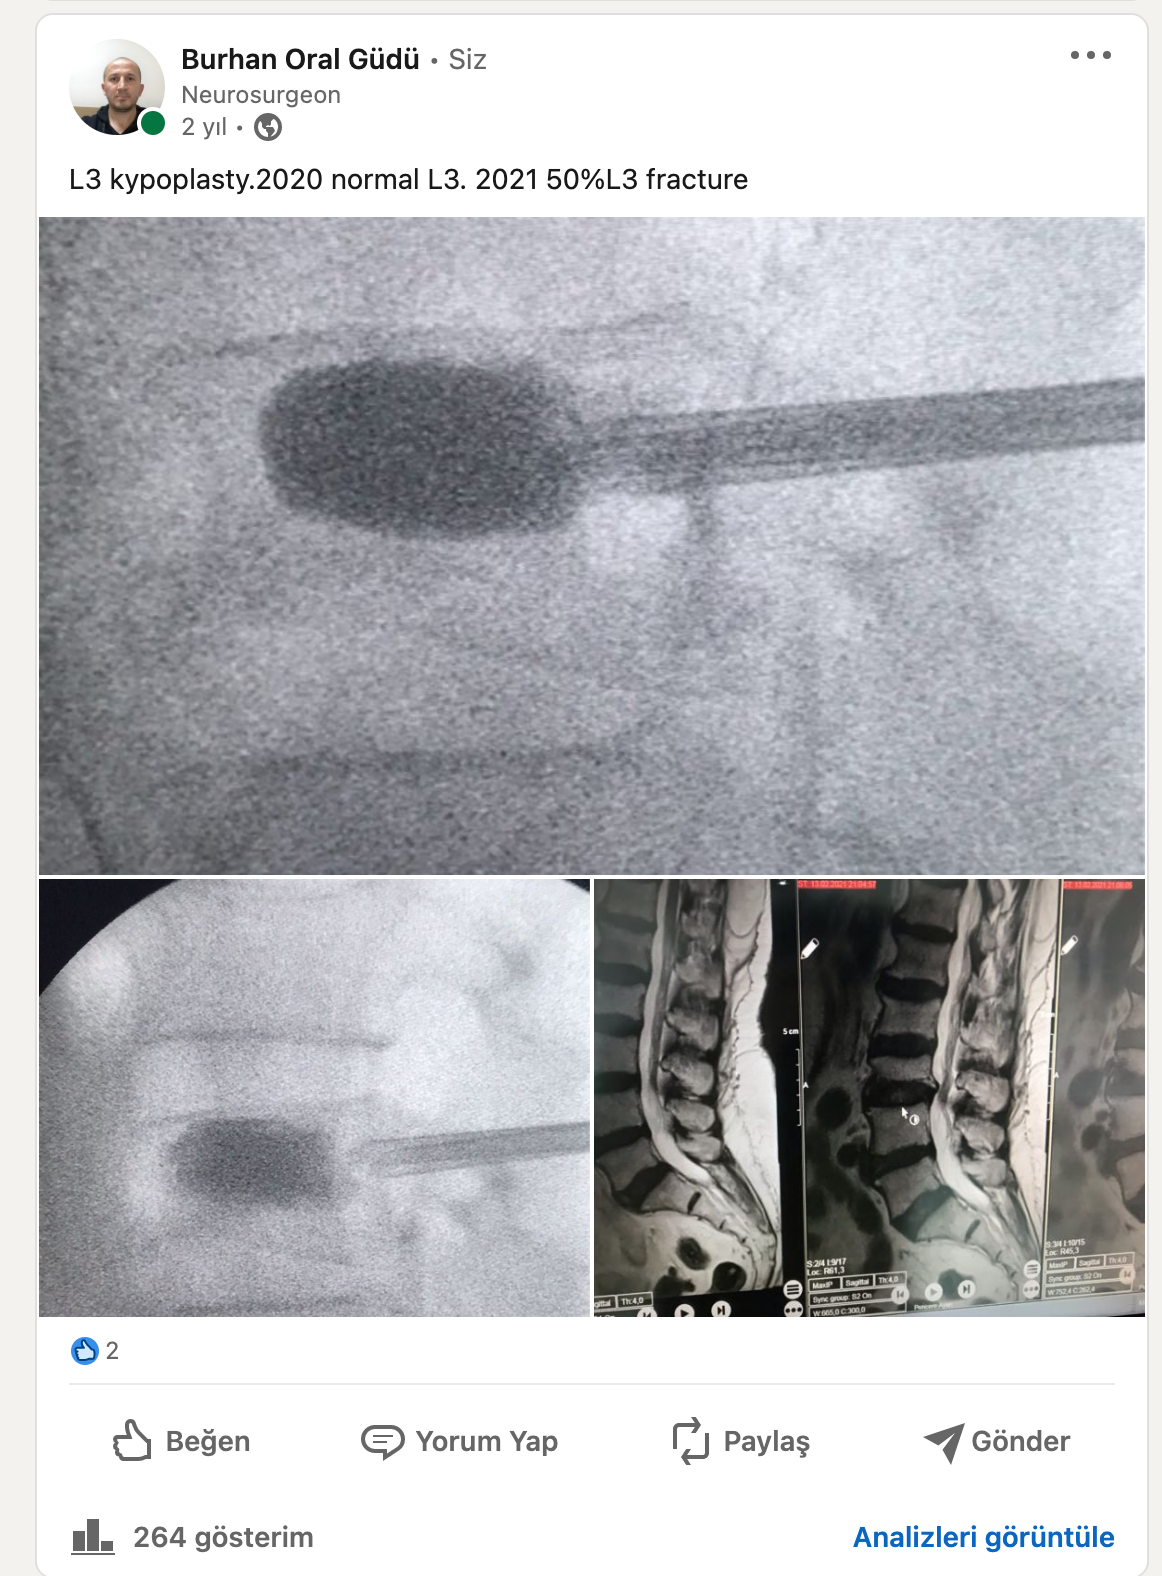

Kifoplasti - Vertebroplasti Nedir